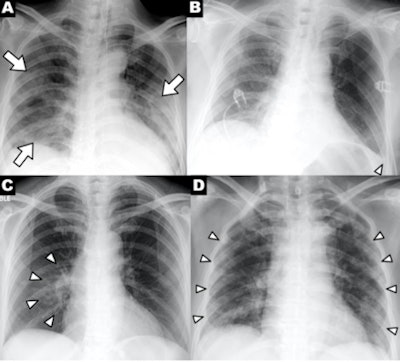

The researchers analyzed images from 64 patients who were seen at four Hong Kong hospitals from January-March 2020. They found that signs of COVID-19 on chest radiography were similar to those of CT: bilateral, peripheral consolidation and/or ground-glass opacities. Consolidation was the most common finding on x-ray in 47% of patients, while ground-glass opacities were found in 33%.

Clinical features on radiography. What features on x-ray are indicative of COVID-19? Chest radiography can show patchy or diffuse asymmetric airspace opacities that are similar to pneumonia caused by other coronaviruses, according to a March 23 article by Dr. Jonathan Rodrigues, PhD, and colleagues in Clinical Radiology.

Meanwhile, researchers from the University of Washington in Seattle have provided a list of the top five findings on chest x-ray of COVID-19. The most common finding was bilateral reticular nodular opacities, found in 52% of cases, followed by ground-glass opacities in 48%. Some 72 hours after admission, these findings rose to 86% for reticular nodular opacities and 67% for ground-glass opacities, they wrote in a study published March 19 in JAMA.